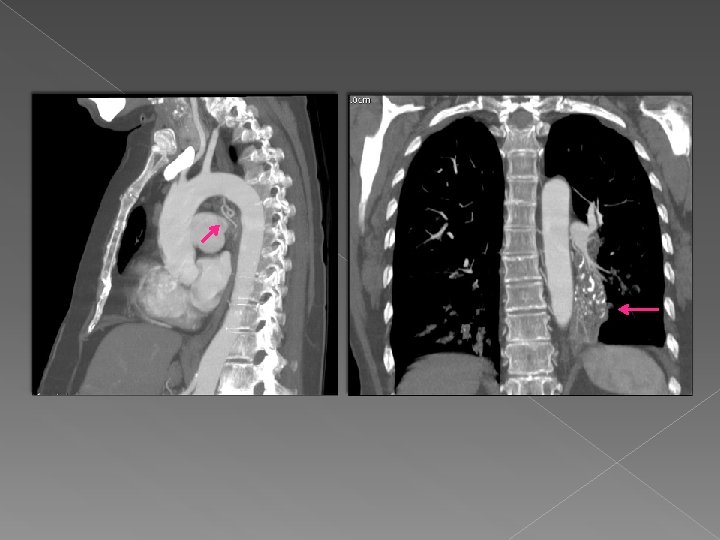

Caso 1 Paciente de 62 años en estudio por masa en LID y hemoptisis.

Caso 1 Paciente de 62 años en estudio por masa en LID y hemoptisis. Tras el reformateo multiplanar se visualiza en LID una masa con centro necrótico y áreas de abscesificación en su interior.

Valor de VR : se visualiza la arteria aferente que se origina en

Valor de VR : se visualiza la arteria aferente que se origina en la aorta y se dirige a la masa con un drenaje venoso a la vena pulmonar inferior derecha. Hallazgos sugestivos de secuestro pulmonar intralobar.

Drenaje venoso Secuestro pulmonar